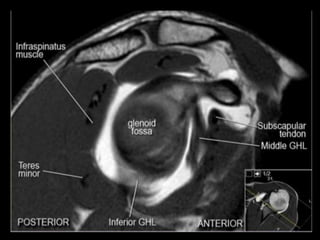

• 120.